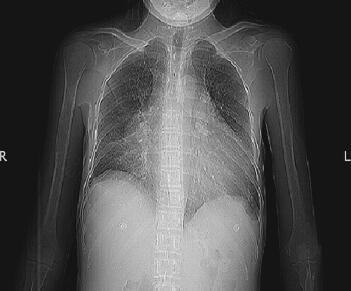

患者于4月12日转入病房治疗。当天实验室检查:血常规:WBC 10.09×109/L,N 80.4%,RBC 4.06×1012/L,ALB 94g/L;生化ALB 33.6g/L,γ-GT 69IU/L,其余异常生化指标均好转;心电图较前无明显变化;胸片较前无明显变化(图1);胸部CT:大量心包积液,左肺中叶密度增高影(图2)。

图1 胸片